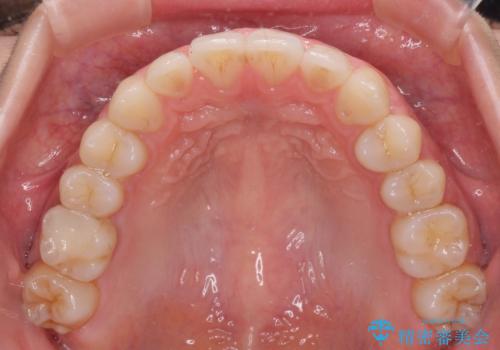

1日22時間の装着時間をしっかり守ってくださったので、予定していた1年よりも早く治療を終えることができました。

インビザライン矯正特有の奥歯がしっかりと咬合しない感覚も改善され、大変満足していただきました。